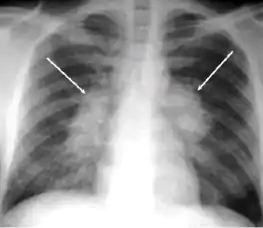

2. Any cavitary lesion - Lucency (darkened area) within the lung parenchyma, with or without irregular margins that might be surrounded by an area of airspace consolidation or infiltrates, or by nodular or fibrotic (reticular) densities, or both. The walls surrounding the lucent area can be thick or thin. Calcification can exist around a cavity.

Chest X-ray of a person with advanced tuberculosis: Infection in both lungs is marked by white arrow-heads, and the formation of a cavity is marked by black arrows.